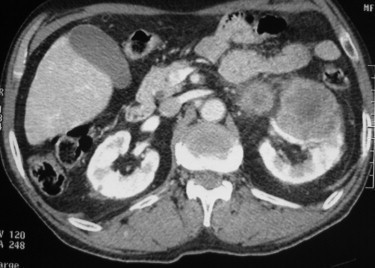

Question 5: Quelle interprétation faites-vous de cette tomodensitométrie abdomino-pelvienne ?

L’examen présenté est un TDM abdomino-pelvien en coupe transversale avec injection de produit de contraste au temps veineux.

On retrouve sur la coupe présentée :

une volumineuse masse tissulaire rénale gauche.

On ne retrouve pas sur la coupe présentée :

de thrombus veineux (veine rénale ou veine cave inférieure) ;

d’adénopathies ;

de seconde tumeur rénale gauche ou droite ;

de nodule hépatique ou pulmonaire.

Au total, sur la coupe présentée, on conclut à un cancer localisé du rein gauche.

L’examen complet de la TDM ne retrouve pas d’autres anomalies.